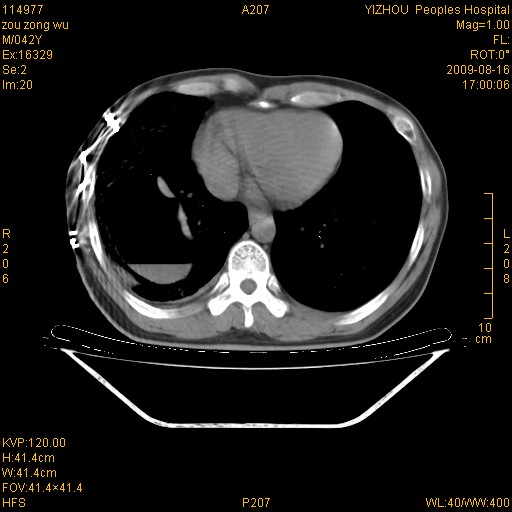

以下是引用zjzjr在2009-8-17 10:42:00的发言:[br]右侧间质性肺炎伴纤维化,右肺下叶肺囊肿伴感染(不除外外伤后引起),右肺野及胸壁软组织\\肝内见多发斑点状,中枪了吧.右侧胸膜肥厚\\粘连.